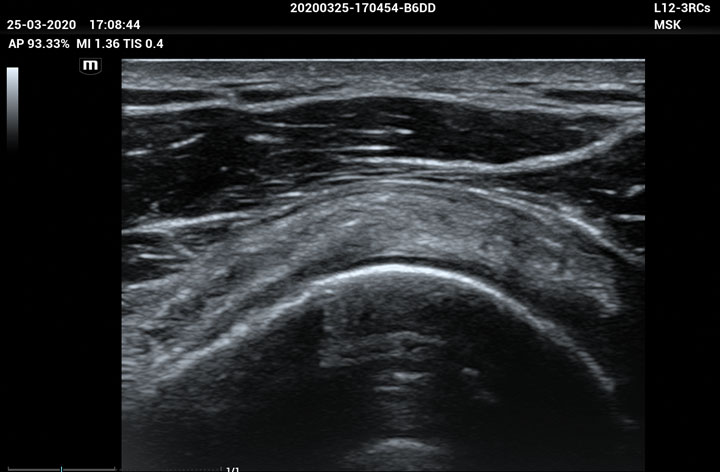

The ME8 Ultrasound System has been thoughtfully designed to overcome the obstacles clinicians face in today’s challenging healthcare environment. Powered by our groundbreaking software-based beamformer technology, ZONE Sonography® Technology+(ZST+), the ME8 Ultrasound System empowers decision-making by providing end-users best-in-class image quality and access to a comprehensive suite of workflow enhancement tools.

Advanced Technologies

Enhancing Clinical Confidence